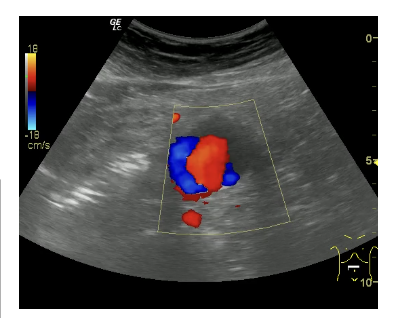

Informe: Hígado de tamaño y ecogenicidad normal. Vesícula distendida con 2 litiasis de 2 x 3 mm en su interior. Páncreas y bazo de ecoestructura normal. Ambos riñones de tamaño, ecogenicidad en rango, diferenciación corticosinusal. Vena porta, cava inferior y aorta en el área del lóbulo hepático izquierdo de calibre normal. Aneurisma de aorta abdominal descendente hasta su bifurcación de ambas iliacas de 3.29 cm en su eje trasversal con engrosamiento de pared posterior.

Desde el seguimiento realizado por el Servicio de Cirugía vascular se observa un crecimiento paulatino de 0,6 cm en 6 meses por lo que se decide intervenir quirúrgicamente.

La ecografía en Atención Primaria se utiliza para la visualización de órganos principales además de grandes vasos abdominales. Por suerte, la observación a nivel abdominal de la aorta descendente es sensible para detectar aneurismas a este nivel. La disponibilidad de la misma así como el conocimiento de dicha técnica facilitan el diagnóstico, tratamiento precoz y disminución de su mortalidad.